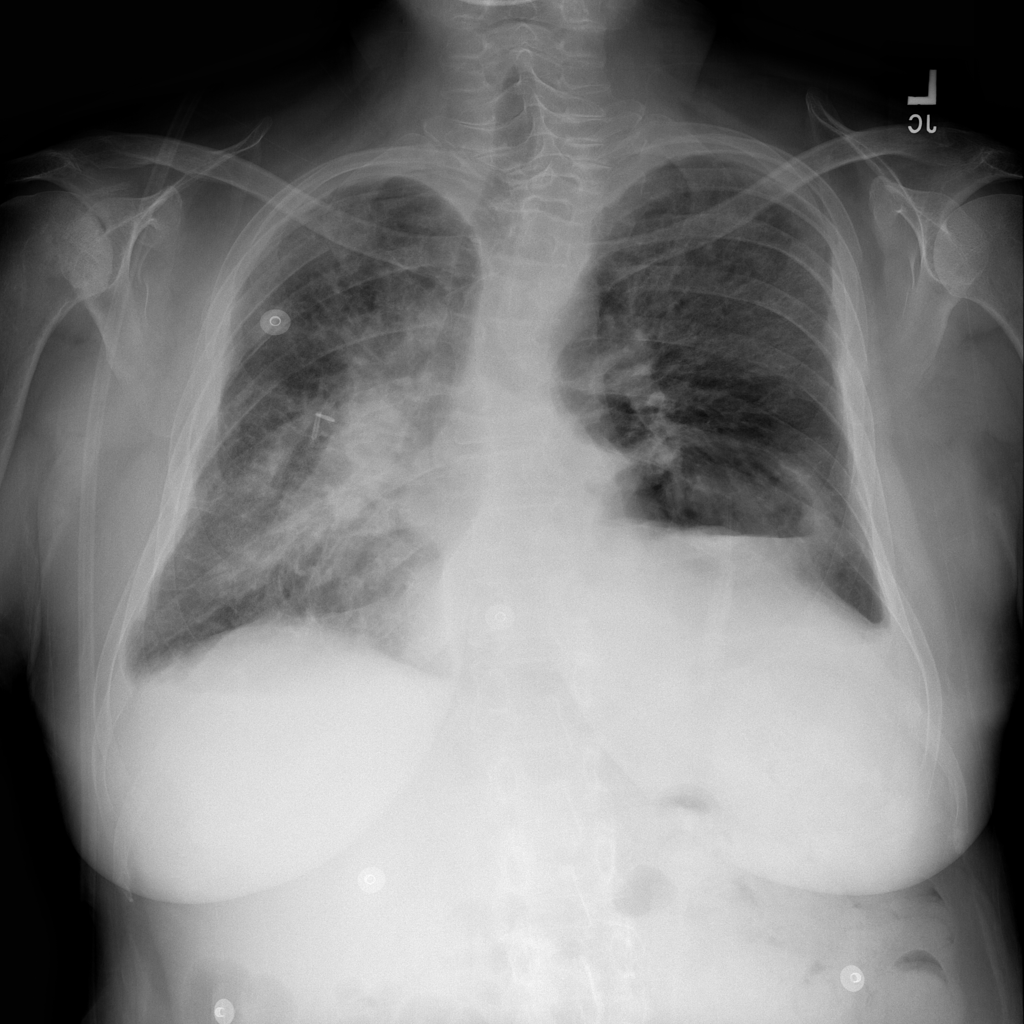

PAT-4F7E · IMG-000Hernia

PAT-4F7E · IMG-000

PA